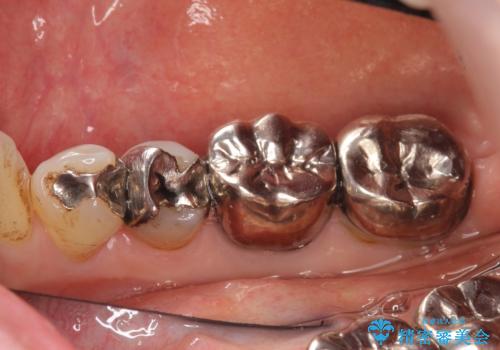

- 右下の古い銀歯のやり替えを希望された方の症例です。

口腔外から見えやすい 4 番目、5 番目の歯はセラミックによる審美的な治療を行い、6 番目、 7 番目の奥歯 2 歯は適合性に優れたPGA(ゴールド)クラウンによる治療を行いました。